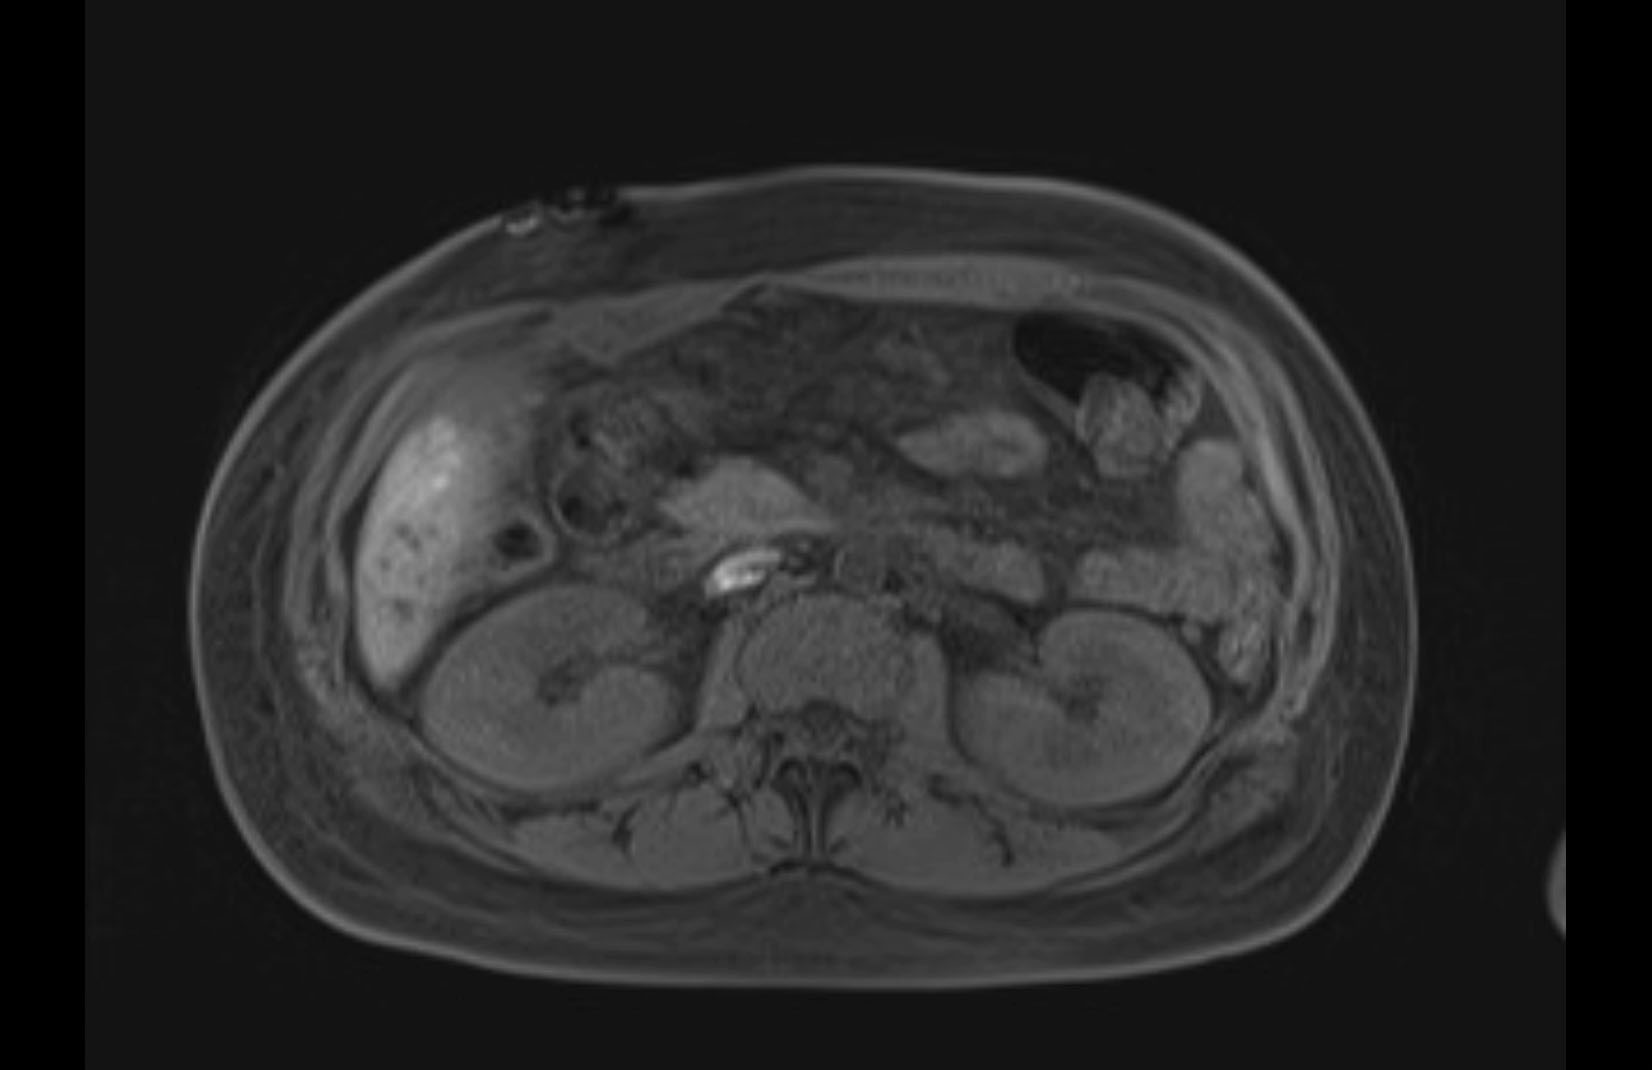

MRI T1

MRI T2